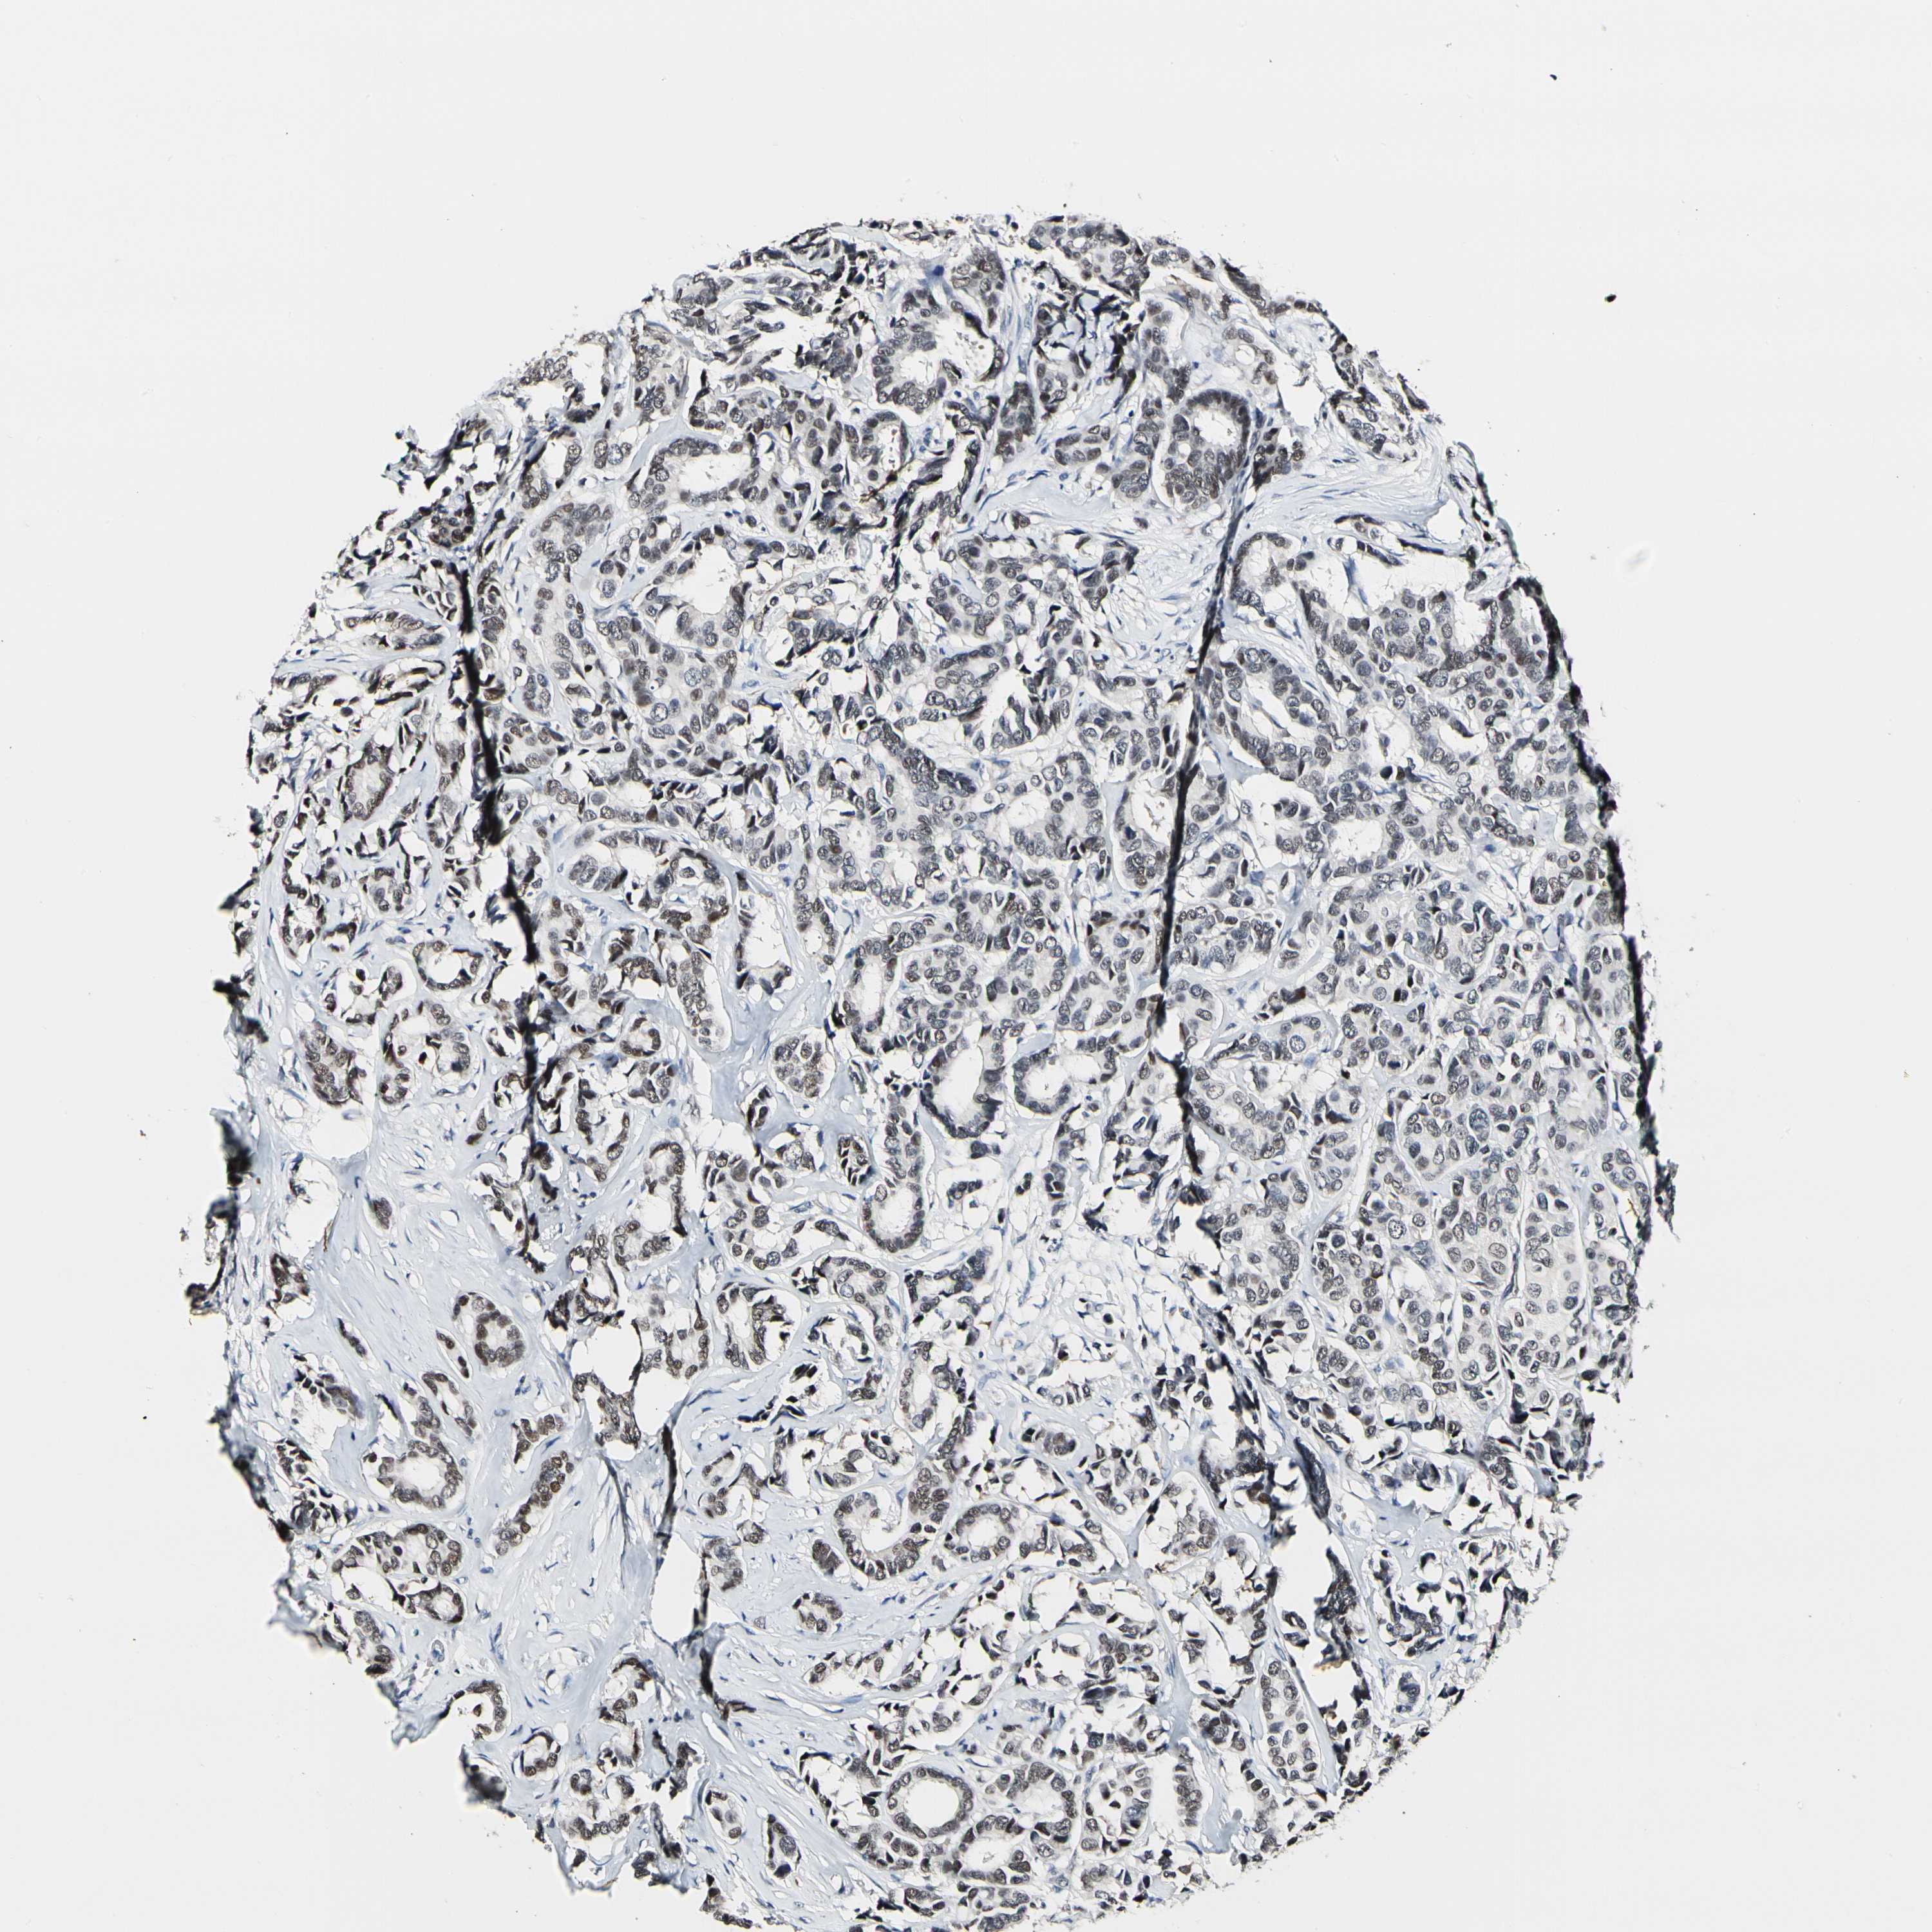

CANCER BREAST CANCER Show tissue menu

BRCA TCGA BRCA VALIDATION PROTEIN EXPRESSION